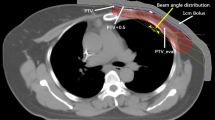

VMAT and IMRT plans

To acquire the necessary data for our study, we obtained computed tomography (CT) images of the upper body of the RANDO phantom (CIRS Inc., Norfolk, VA, USA), a widely-used anthropomorphic phantom for radiation dosimetry measurements, using a Discovery RT scanner (GE Healthcare, Waukesha, WI, USA) with a tube voltage of 120 kVp, tube current of 450 mA, and slice thickness of 2.5 mm. Treatment plans were then created using the Eclipse treatment planning system version 16.1 with the AAA dose calculation algorithm from Varian Medical Systems for both the TrueBeam and Halcyon linear accelerators (linac). Four plans were designed for Halcyon with FFF beam and for TrueBeam with FF beam: intensity-modulated radiation therapy with seven fields (7F-IMRT) and volumetric modulated arc therapy with two arcs (VMAT-2A), four arcs (VMAT-4A) and six arcs (VMAT-6A), as shown in Fig. 1. The prescribed dose for the entire left breast was set at 200 cGy for all plans (Table 1).